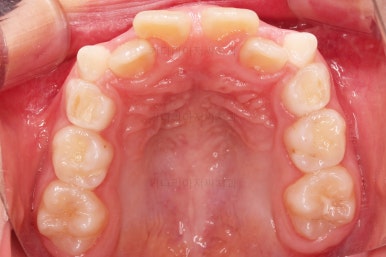

위턱뼈가 가로로 넓어지니 앞니 사이에도 공간이 많이 생겼네요.

부분적으로 교정장치를 부착해서 당사자가 제일 고치고 싶어햇던 앞니 부분을 가지런하게 하기 시작했어요.

위턱뼈가 앞으로도 점점 나와서 처음 보다는 반대교합 경향이 개선되고 있는게 보이네요.

앞니도 굉장히 가지런해졌고요.